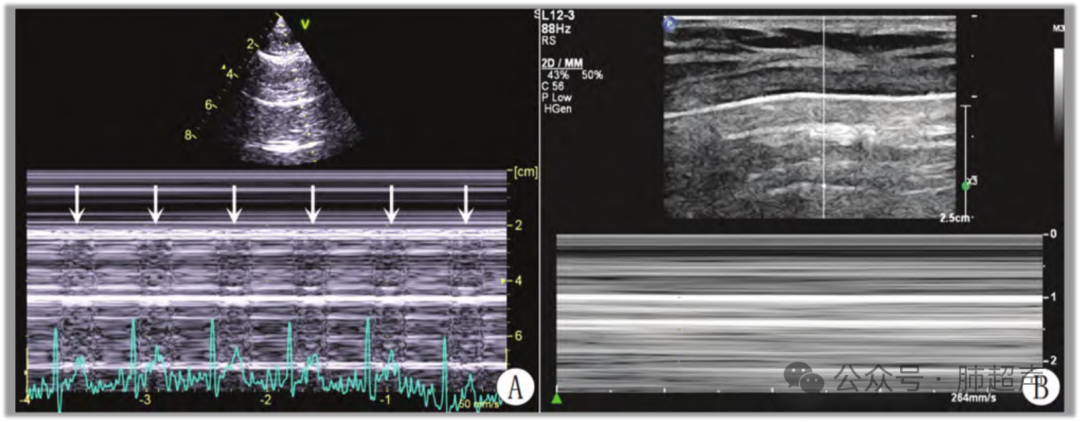

(1) 胸膜后方彗星尾征、B线及肺实变,以及胸膜滑动征、胸膜搏动征、海岸征均为排除诊断气胸的超声征象(图5A)

(2) 肺点征和平流层征为气胸的特异性征象。肺点征提示局限性气胸,患侧气胸未完全将胸膜分离;单肺完全显示平流层征及胸膜无滑动(无肺点征)提示患侧气胸完全包裹肺组织,两层胸膜完全分离(图5B)

图片

图5  气胸超声表现

注:A. M型超声示心电图R波后胸膜同频搏动,可排除气胸;B. 气胸在M型超声显示为平流层征。